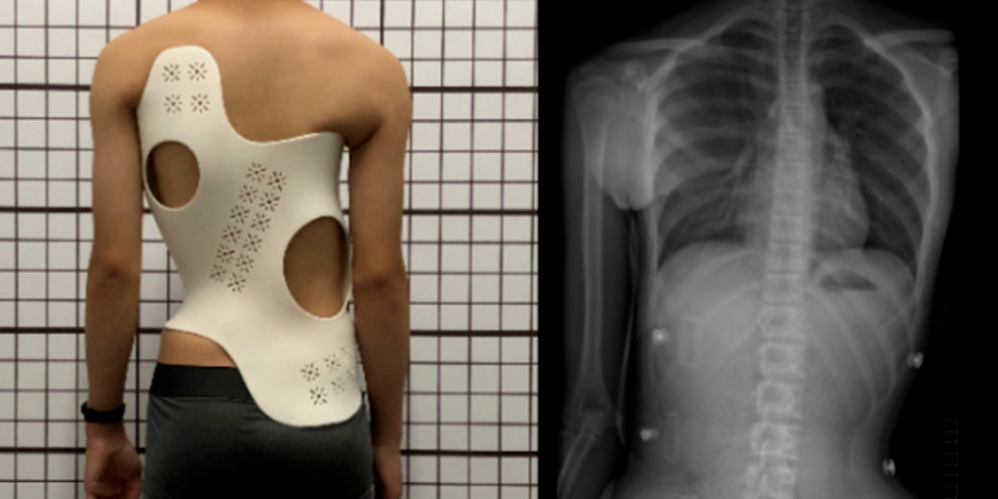

脊柱側彎是一種常見的脊柱畸形疾病,臨床上常用立位X光片來評價脊柱側彎的嚴重程度,然而這種傳統(tǒng)的評估方法并不能全面反映脊柱的三維形態(tài)。在此背景下,三維重建與3D打印技術為我們提供了全新的視角和可能性。

- 三維評估:通過CT掃描和三維重建,我們可以得到患者脊柱的三維模型,更全面、直觀地評估脊柱側彎的嚴重程度及其對附近組織的影響。

- 手術規(guī)劃:手術醫(yī)生可以利用3D打印出的脊柱模型,實際觀察和模擬手術步驟,從而進行精確的手術規(guī)劃。

- 病患教育:通過向患者展示他們自己脊柱的3D打印模型,醫(yī)生可以更有效地解釋病情,幫助患者理解疾病狀況和手術方案。